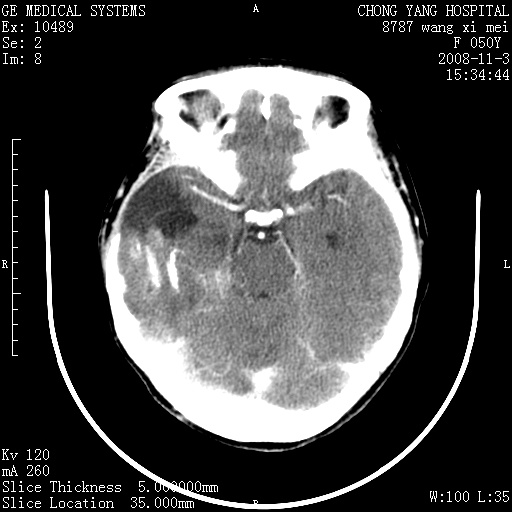

右颞骨局限性缺如,局部脑组织无外隆。右颞叶可见片状脑脊液样低密度影,边缘较清,右侧侧脑室三角区可见一块状等密度影,且伴有强化,余未见明显异常改变。

考虑:右大脑术后改变伴肿瘤复发。

手术后局部片状低密度改变(软化灶),其后方颞叶似等密度病灶,界限不清,内见钙化,有轻度占位效应,但增强后强化之血管走行如常。应不考虑:复发!

应考虑肿瘤复发,右颞顶叶已出现轻度强化肿块.必要时可与原片比较以下.

局部软化灶并钙化;无花边样强化,不象复发